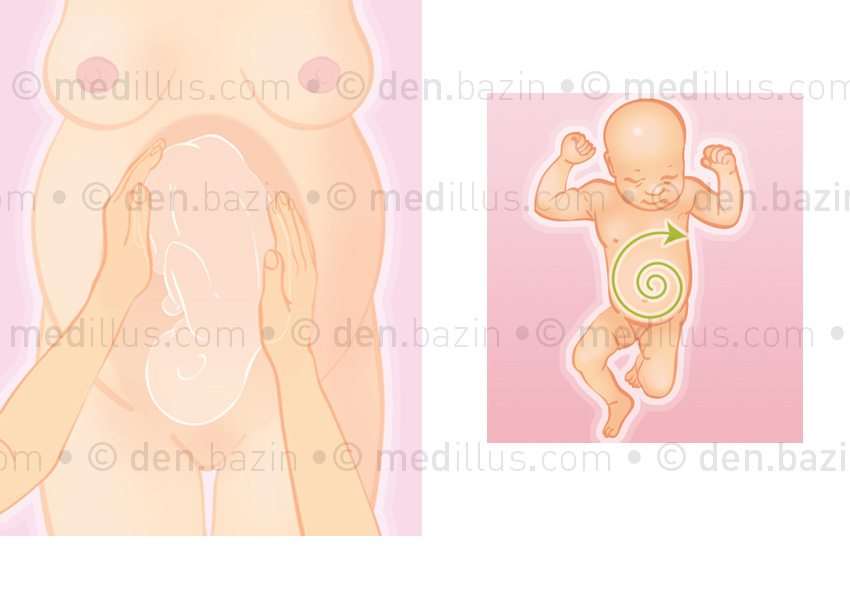

Manœuvre de retournement et massage abdominal du nouveau-né